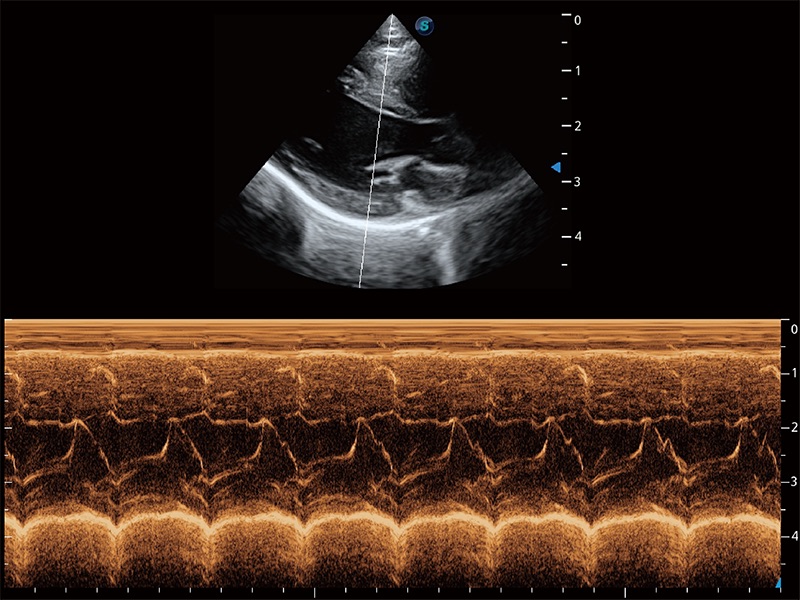

• AMM 解剖M型

通过360度任意调节3条M型取样线,在同一心动周期上观察心脏不同位置的运动曲线,得到准确的心功能测量数据,有效评估心肌运动及左心室功能。

(猫)二尖瓣M型